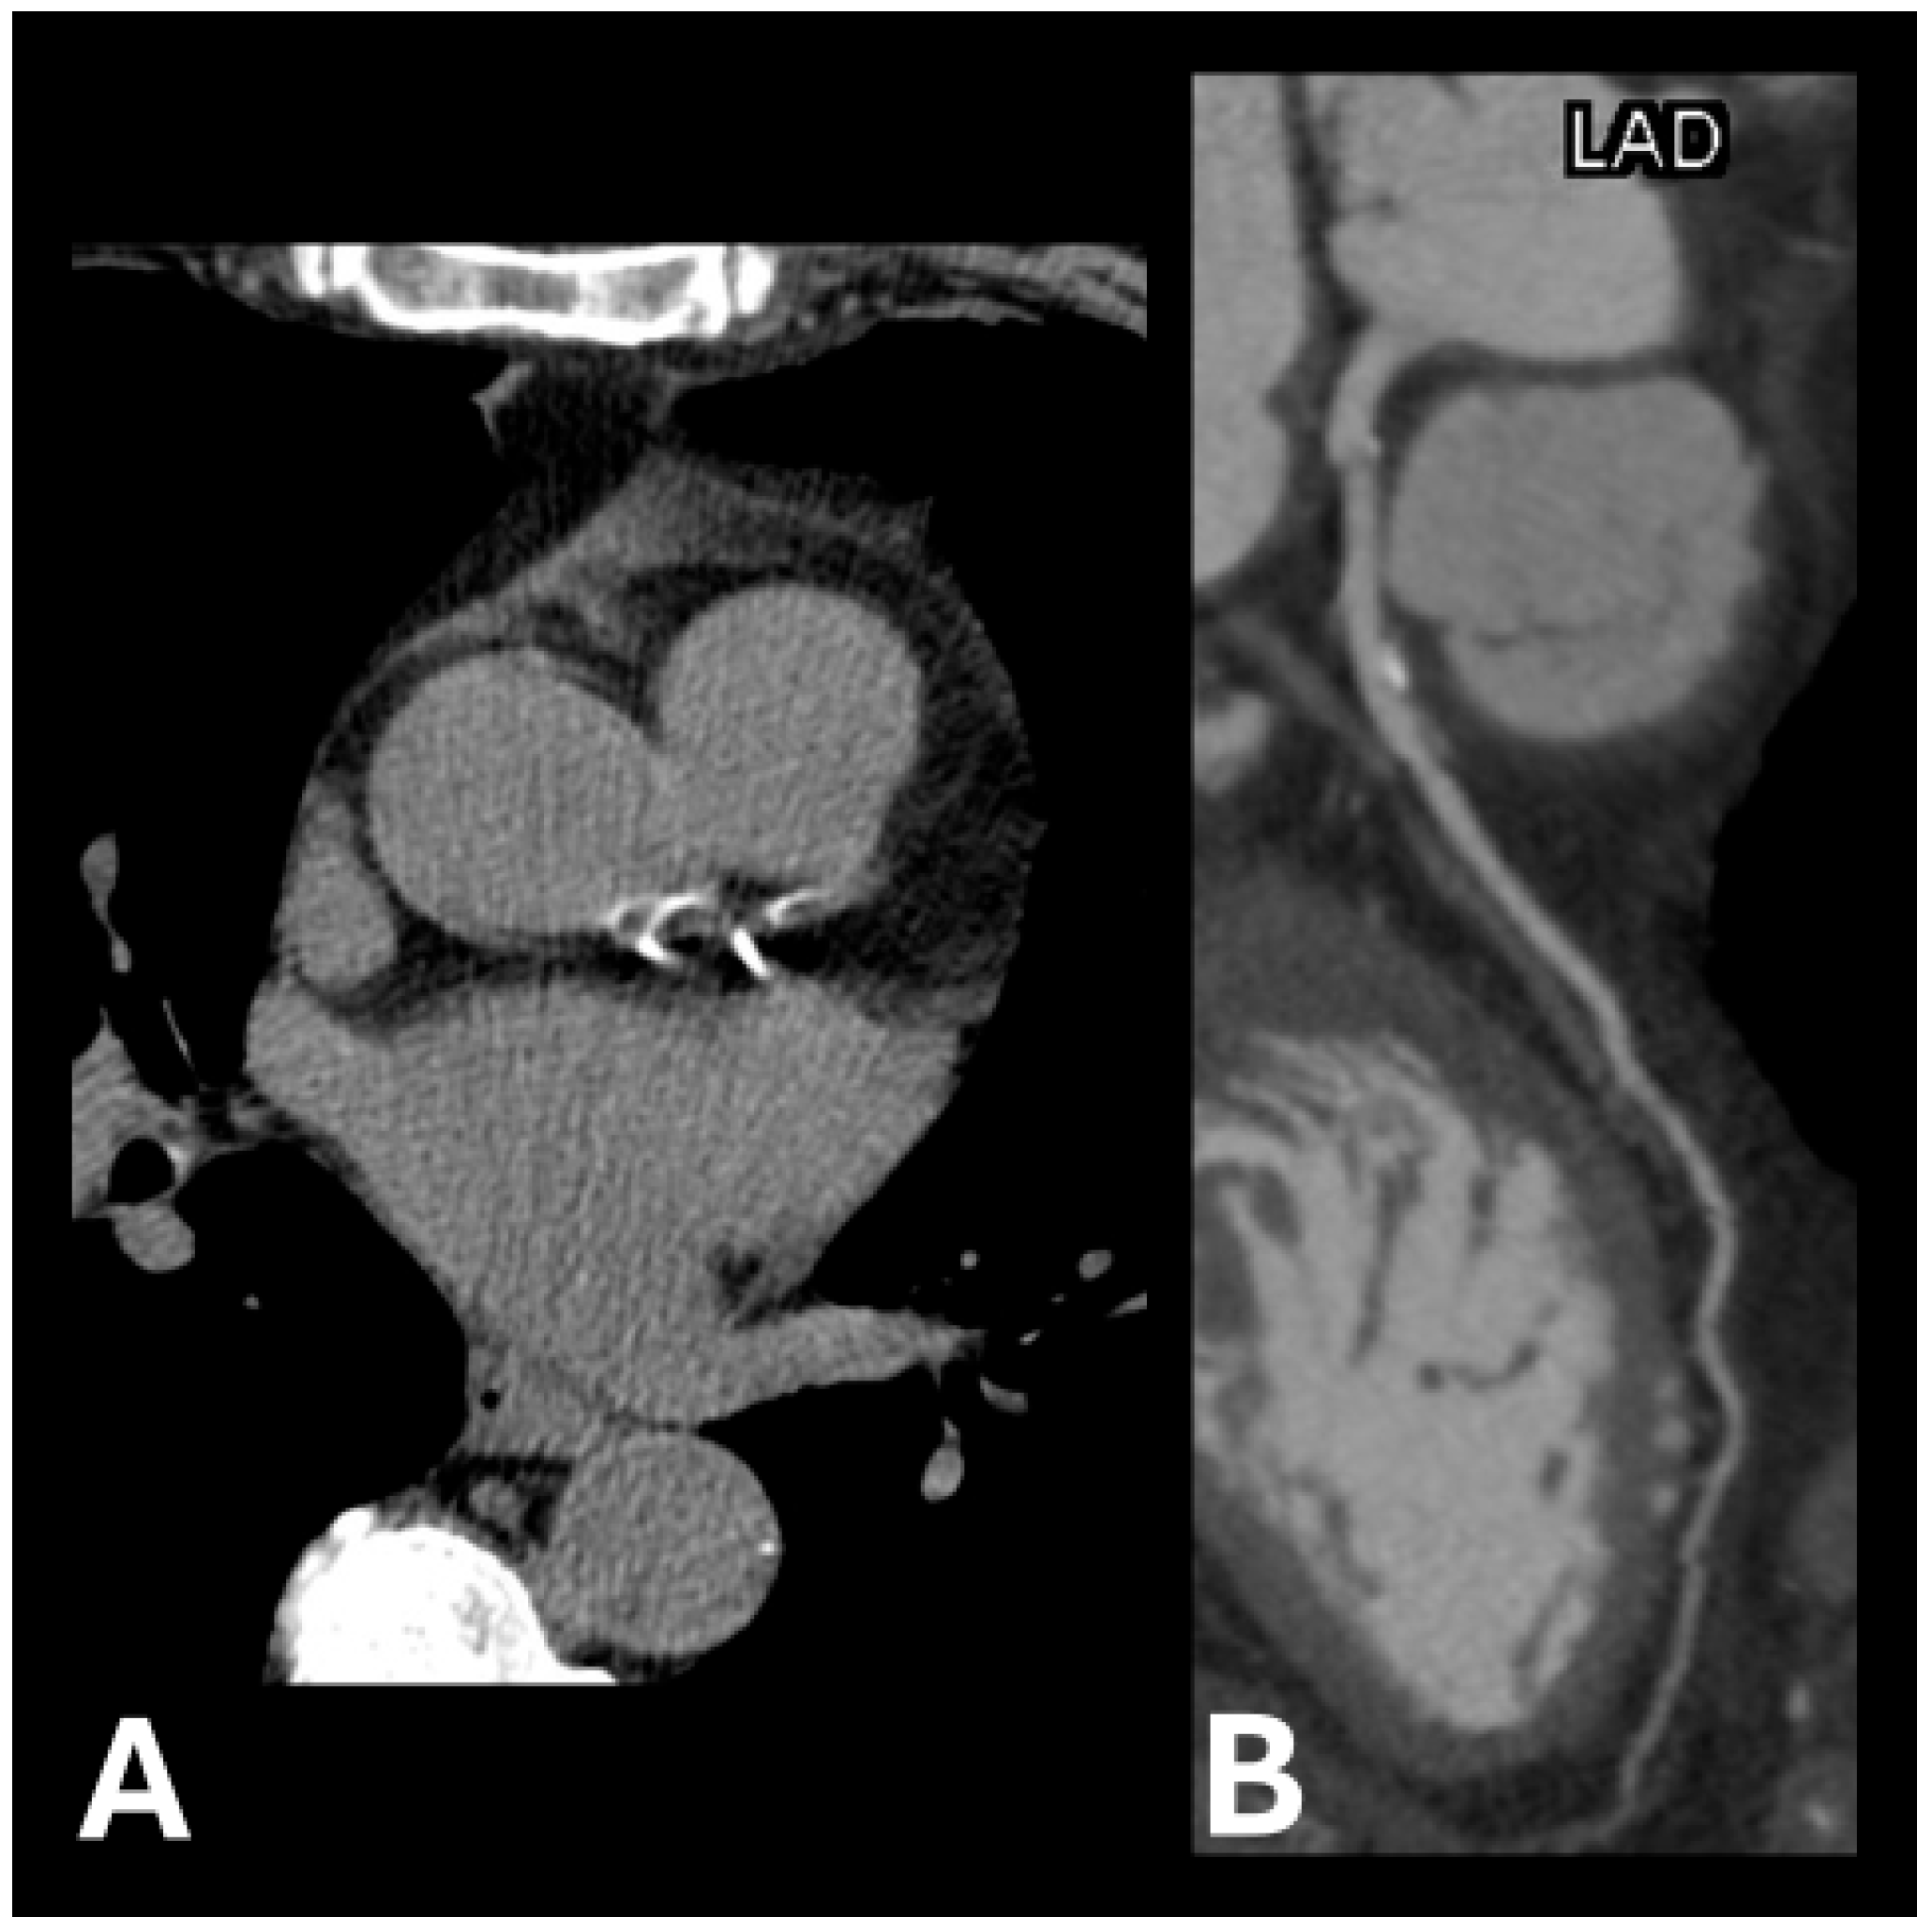

Example images of calcified and non-calcified coronary arteries are shown in Figure 1 and Figure 2, respectively.

Figure 1.

Examples of calcification plaque(s) in (A) left anterior descending artery and left circumflex artery and (B) left anterior descending artery.